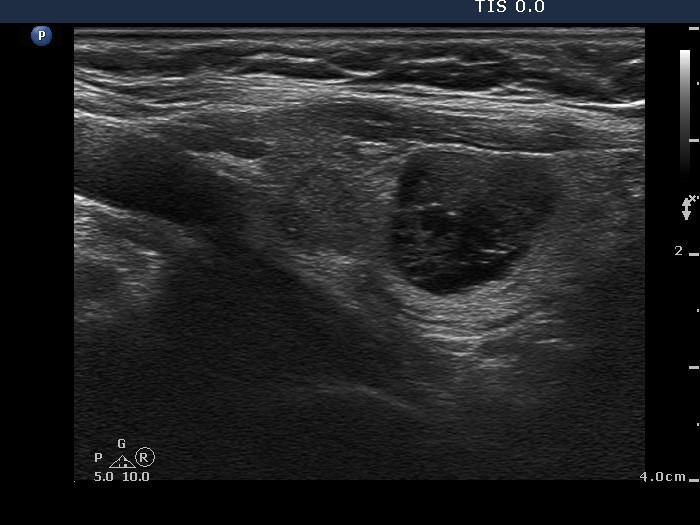

Granulation around surgical thread (histological diagnosis) - case 411 |

Papillary carcinoma (histological diagnosis) - case 779 |

Here is another example of the differential diagnostic problem caused by granulation around surgical thread. Again, there is no difference between the ultrasound presentations of these cases except for the vascularization. The right, malignant case cannot be a granulation around surgical thread which is always avascular; however, this is not a great revelation in a patient who has not been operated. Conversely, the lack of vascularization by no means excludes the possibility of a carcinoma.